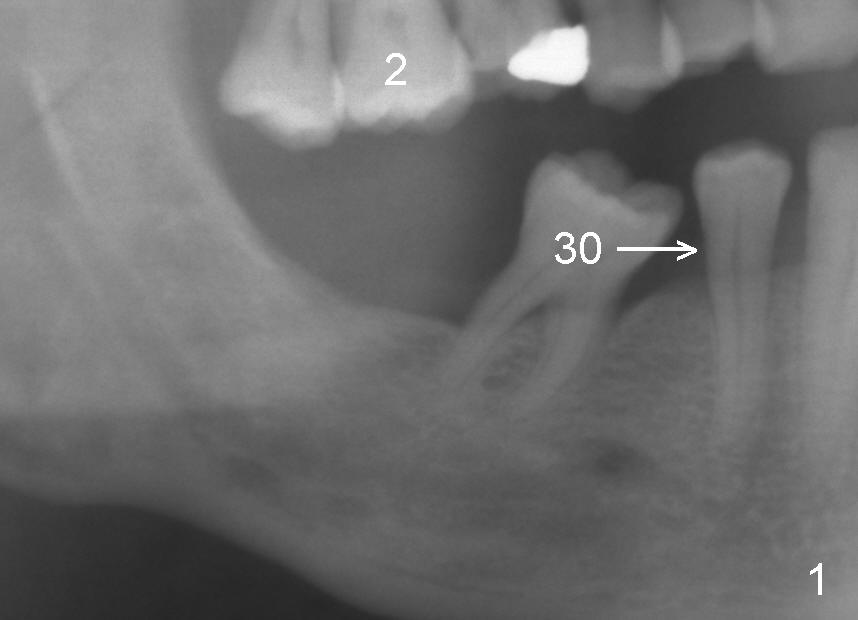

Mr. Liu has lost the tooth #29 for a while. The tooth #30 has shifted mesially (Fig.1 arrow). An implant is placed distal to it (Fig.2). Orthodontics has started to upright the tooth #30, but he does not want to finish the treatment.